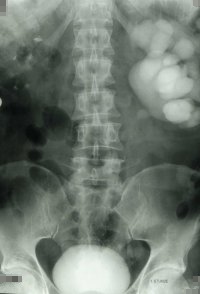

Bei einem fünfjährigen Jungen trat Wochen nach der offenen Pyeloplastik eine Abflussbehinderung auf. Die retrograde Sondierung ergab eine umschriebene Obstruktion. Die in gleicher Sitzung durchgeführte Ballondilatation führte zur Normalisierung der Abflussverhältnisse (Abbildung 15).